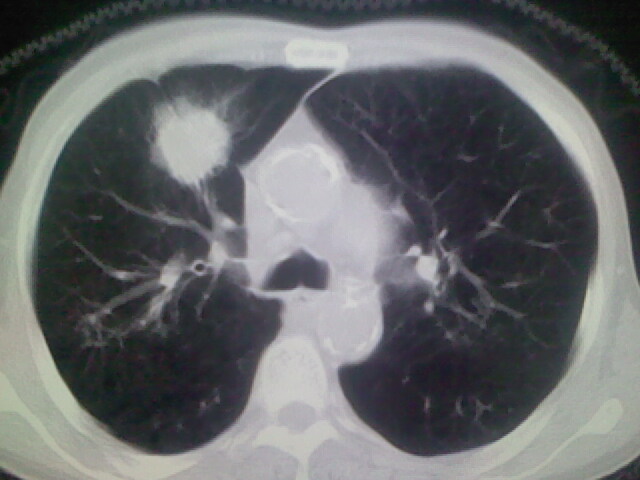

男,70y,胃占位,重度贫血,黑便3月余,伴恶心,纳差,乏力

肺内考虑原发(周围型肺癌)

右上肺周围型肺癌,肝内多发低密度影---转移瘤?建议增强;胃壁明显增厚.

1)考虑右肺上叶周围型肺癌并纵隔及右颈部淋巴结转移,肝脏多发性转移。2)肺气肿。3)冠状动脉及主动脉钙化。